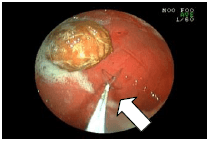

![]() |

ポリープがどんなものか調べるために、ポリープの一部をつまんで持ち帰ろうとしているところです。 検査の結果、このポリープは形質細胞腫(けいしつさいぼうしゅ)というガンだと分かりました。 |